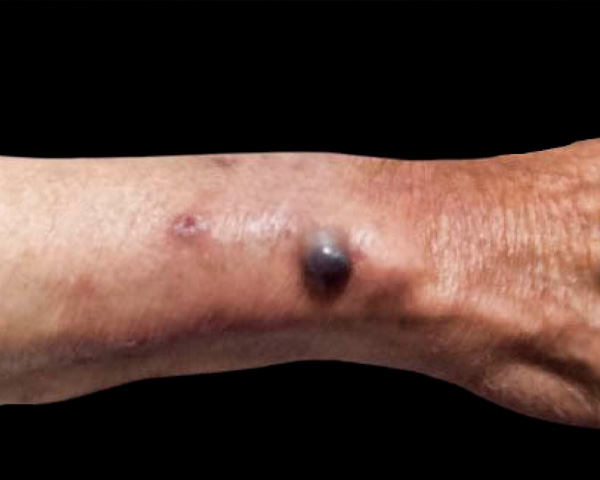

Los tumores dolorosos de la piel son un reto diagnóstico para el médico dermatólogo por su evolución insidiosa e inespecífica. Estas lesiones son poco frecuentes correspondiendo aproximadamente al 2% de los tumores de tejidos blandos cutáneos, además se acompañan de síntomas dolorosos neuropáticos, destacándose la alodinia como síntoma cardinal. A continuación, se describe el caso de un paciente masculino de 76 años que presentó un tumor doloroso solitario de localización poco frecuente en el tercio distal de antebrazo derecho tratado quirúrgicamente. De esta manera se resolvió el dolor asociado y mejoró su calidad de vida.